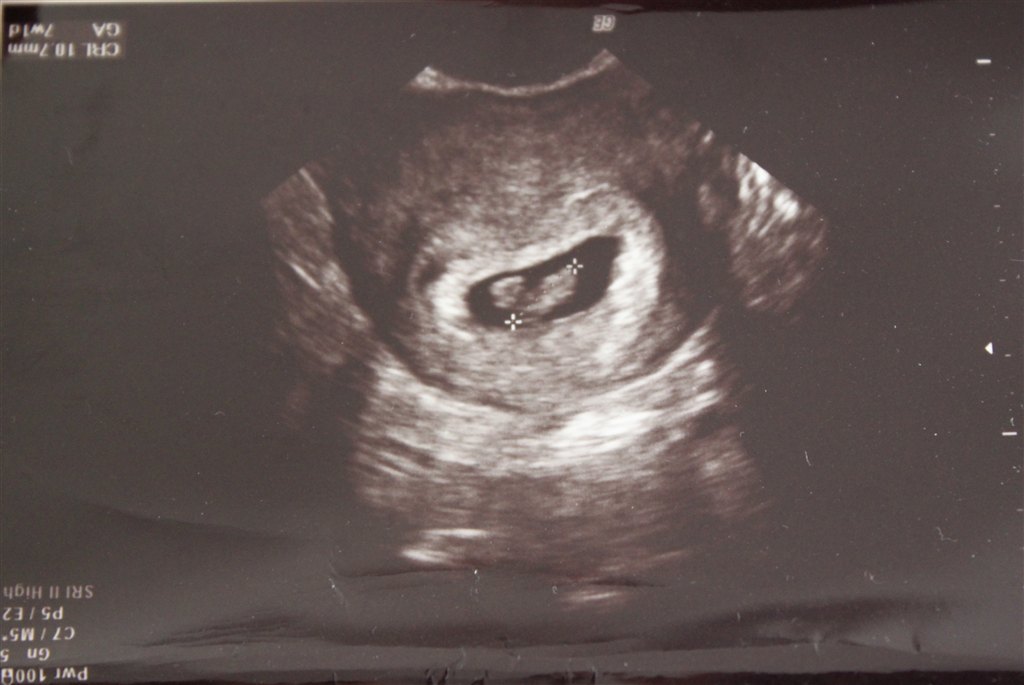

Jeg var til scanning, da jeg var 7+1 (se de vedhæftede billeder).

Den ene af mine havde gemt sig lidt, så den er lidt utydelig

Vedhæftede fotos (klik for at se i fuld størrelse)